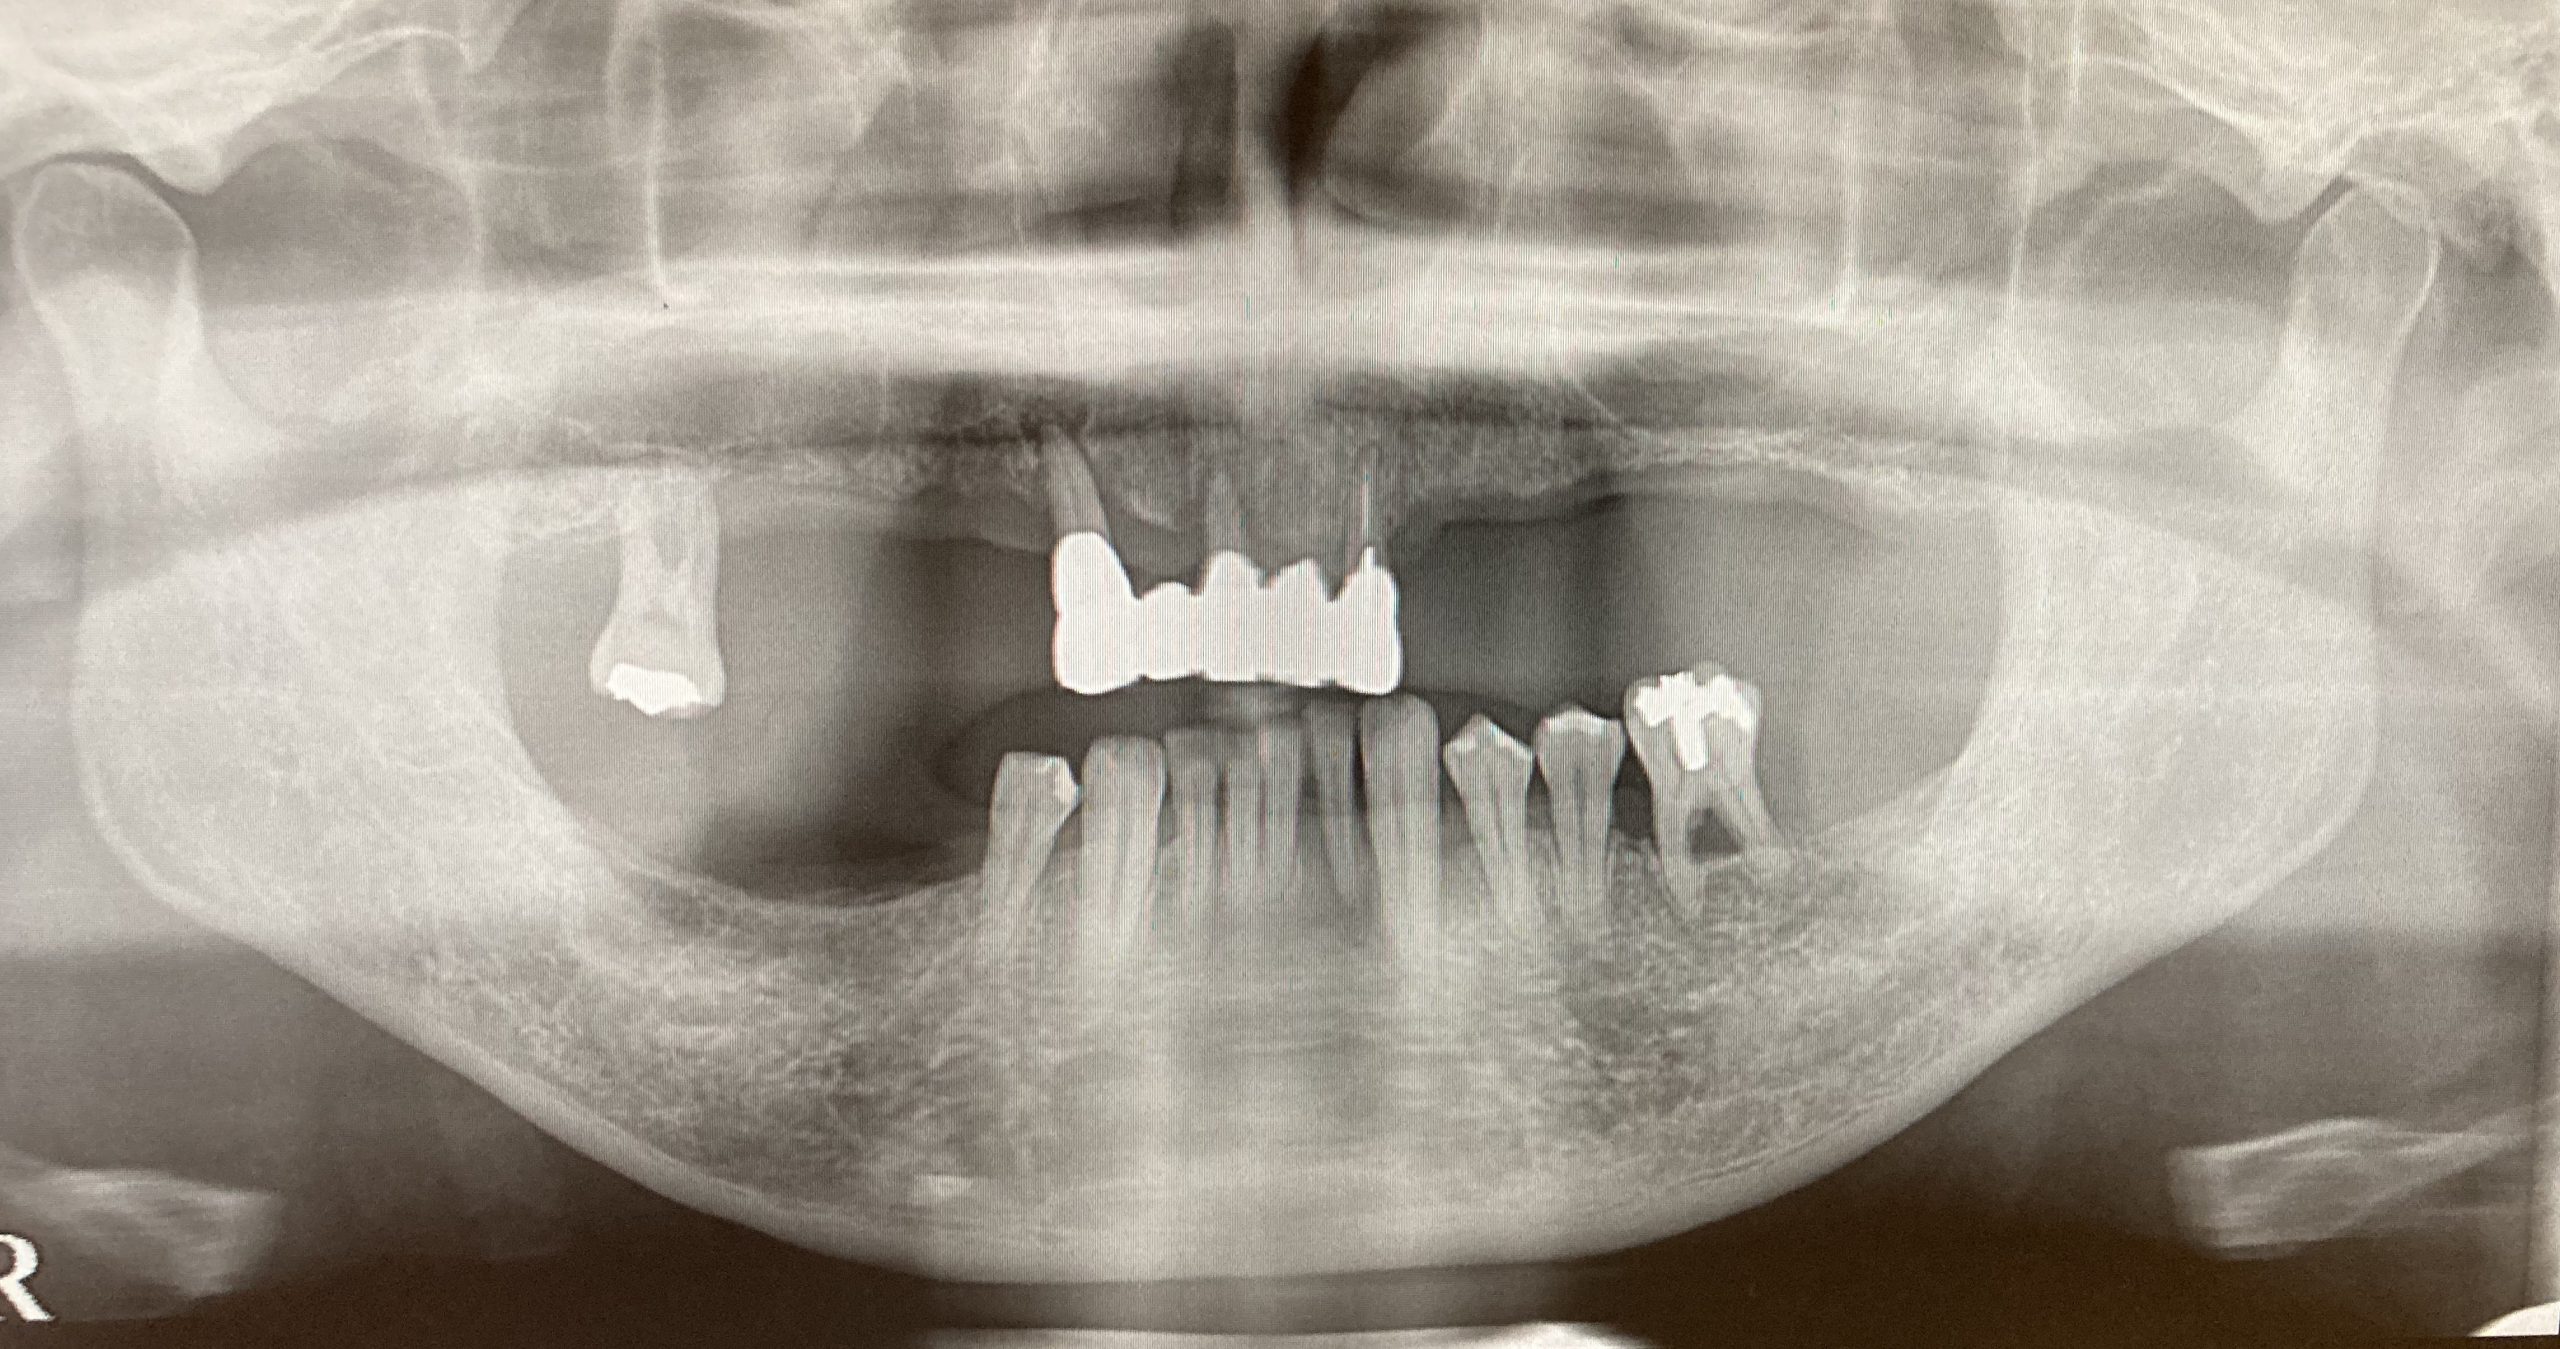

インプラントが4本埋入されたレントゲンになります。